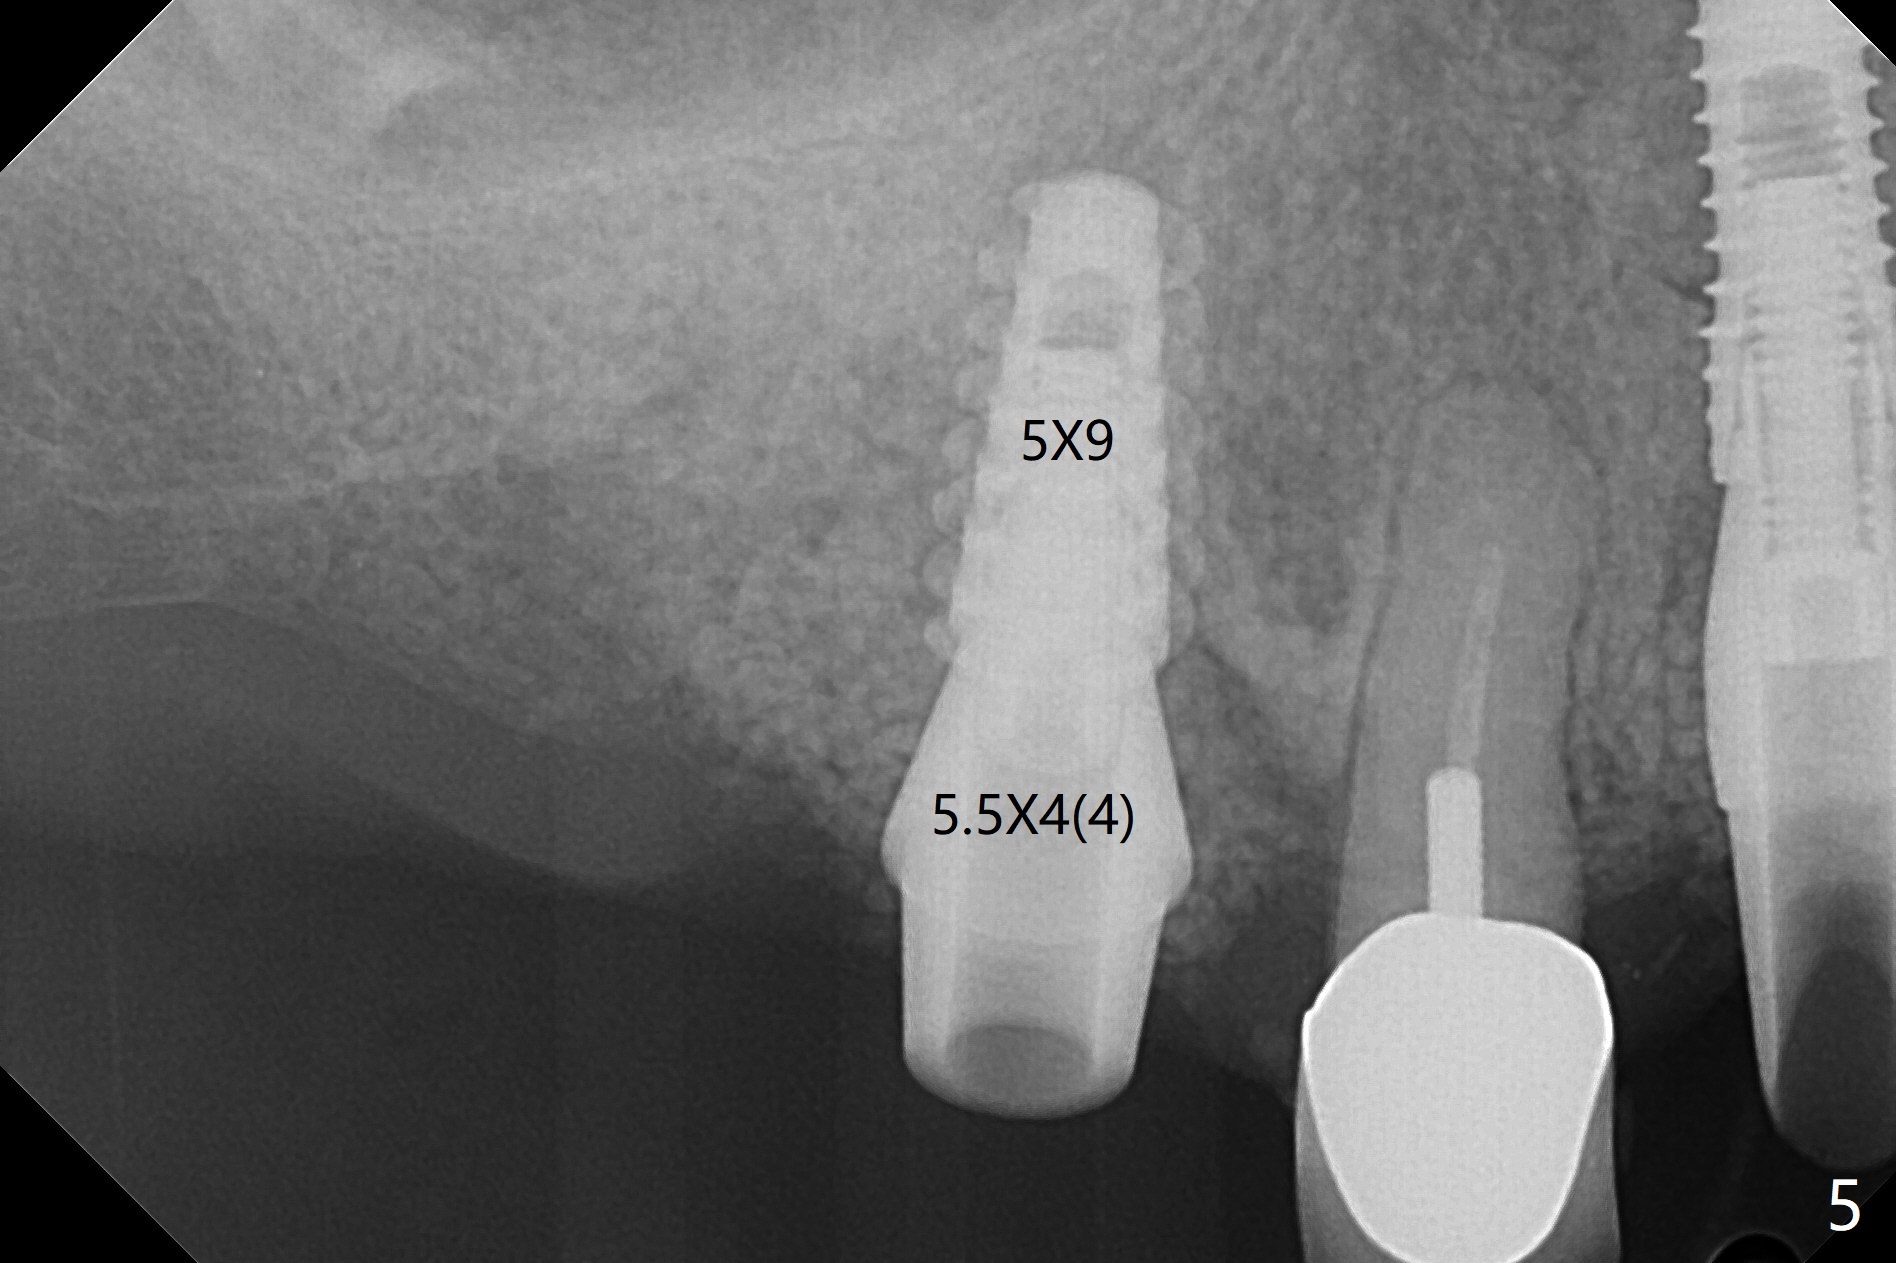

After incision and flap elevation, the crown of the impacted canine is more superficial. With removal of the buccal cortical plate and multiple sectioning of the crown, the latter is removed (Fig.1 *). Further removal of the buccal plate (P) and purchase points, the root (R) is extracted easier. In fact the apex of the root is the deepest (Fig.2). With the guide (Fig.3 G) and 2.2 mm drills, the osteotomy is established. It is pretty shallow. A 3x18 mm drill is used to deepen the osteotomy free hand (mistake: too palatal). When a 3.8x18 mm UF implant is being placed, it cannot be placed deep with the guide. When the latter is removed, the implant seems to be placed too deep and too buccal with <10 Ncm (Fig.4). A 4.5x7(5) mm abutment is placed mainly to correct the trajectory of the implant to certain degree. Placement of the implant at #3 is quite smooth (Fig.5) in spite of severe bone loss and abundant granulation tissue at #3 and 5. The implant at #5 does achieve 2 pointed fixation (Fig.4,6 arrowheads). The most coronal portion of the canine crown is left behind (Fig.6 C).